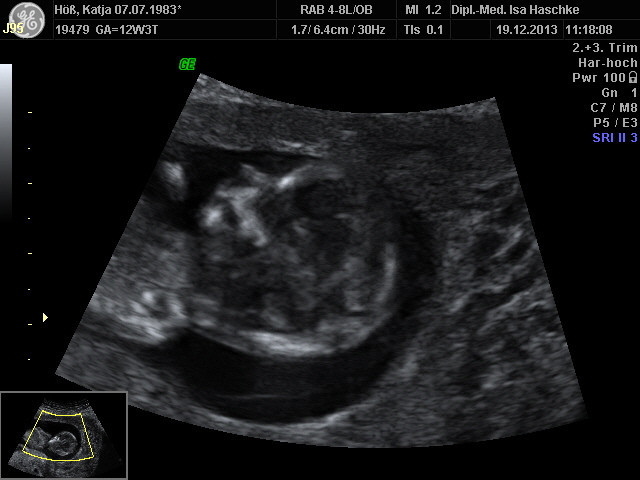

Schwangerschaftswoche 13

Nach unserer Zustimmung und Einverstandnis konnte nun die Nackenfaltenmessung des ungeborenen gemacht werden, am 19.12.2013 wurde diese durchgeführt. Der Befund ist positiv ausgefallen, zu 0,0083 % konnte eine Fehlbildung ausgeschlossen werden, worüber wir sehr glücklich sind.